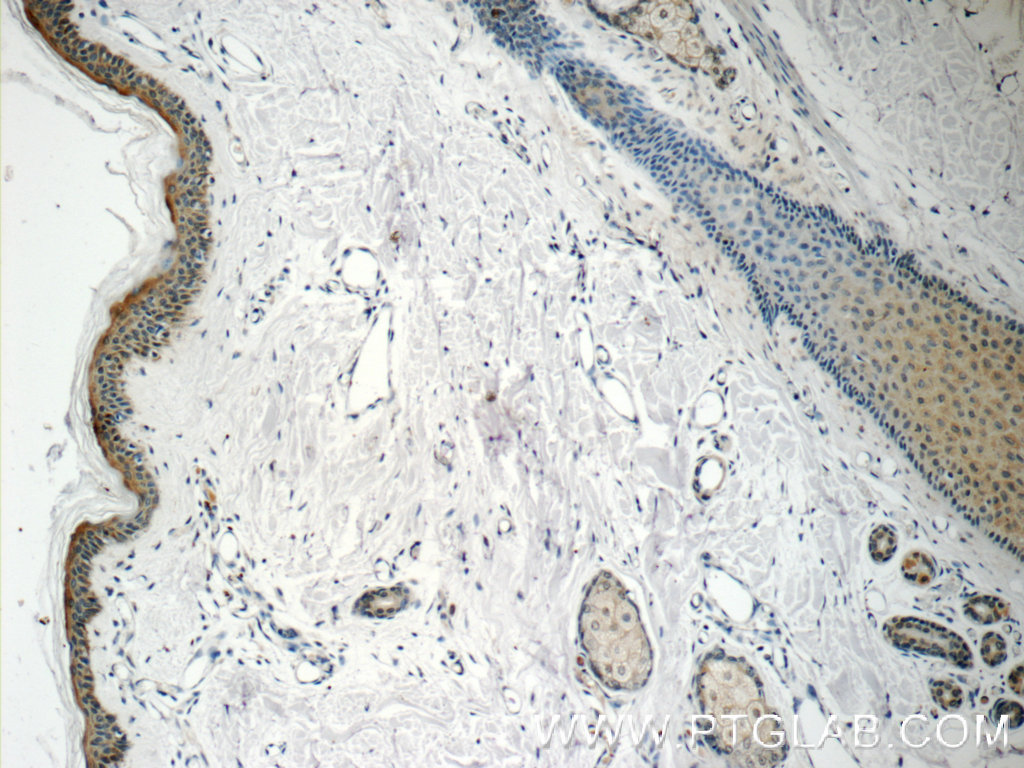

| Positive IHC detected in | human skin tissue Note: suggested antigen retrieval with TE buffer pH 9.0; (*) Alternatively, antigen retrieval may be performed with citrate buffer pH 6.0 |

| Immunohistochemistry (IHC) | IHC : 1:20-1:200 |